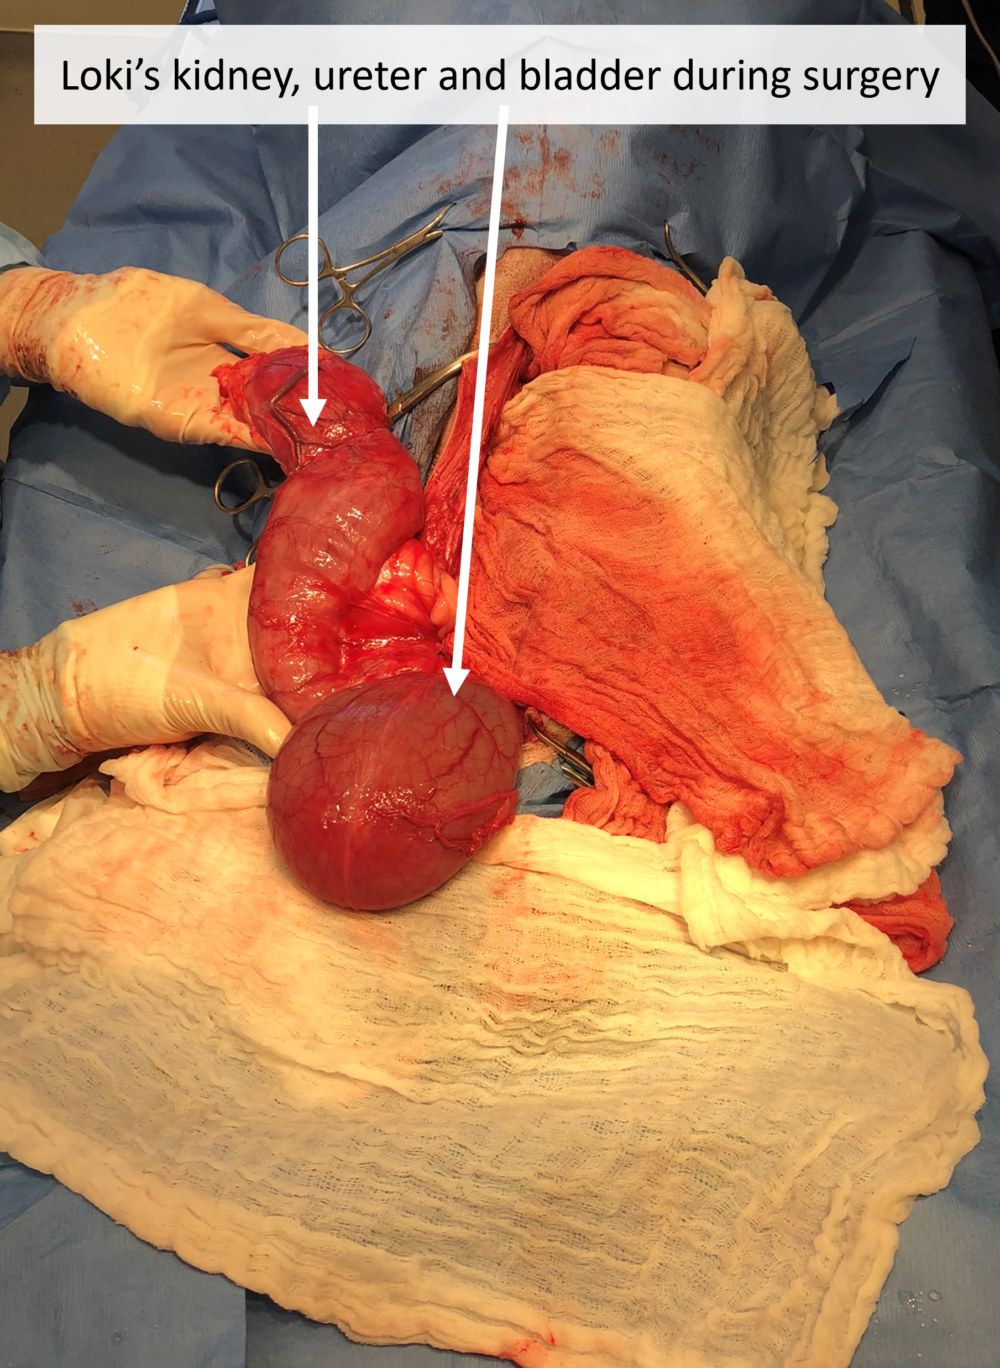

Loki’s Surgery Photos (Warning: Graphic)

Loki has a new lease on life thanks to life-saving surgery from the Idaho Humane Society. Loki was born with a rare malformation of his urinary tract, which caused urine to build up and damage his right kidney. As a result, the ureter — the tube which normally delivers urine from the kidney to the bladder — became stretched to the width of a soda can when it should be the width of a spaghetti noodle. The pressure caused irreversible damage to his kidney, and he was at risk for life-threatening rupture or infection. Our medical team drained nearly 2 liters of urine from his right kidney during Loki’s surgery to prevent immediate rupture. Afterward, we removed the damaged kidney and ureter to prevent this from happening again. Since Loki’s other kidney is healthy and functioning normally, he can now live a perfectly healthy life with one kidney! Loki is now ready for adoption.